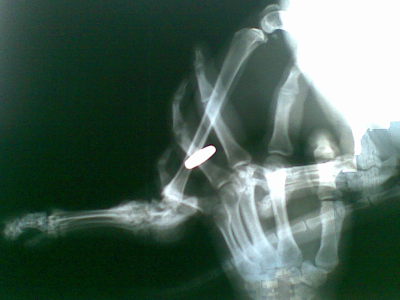

Как принимать остеогенон до или после . . . принимала его, строго соблюдая рекомендации врача . А когда пошла на очередной рентген, то он показал, . . . Что лучше быструм гель или фастум . . .